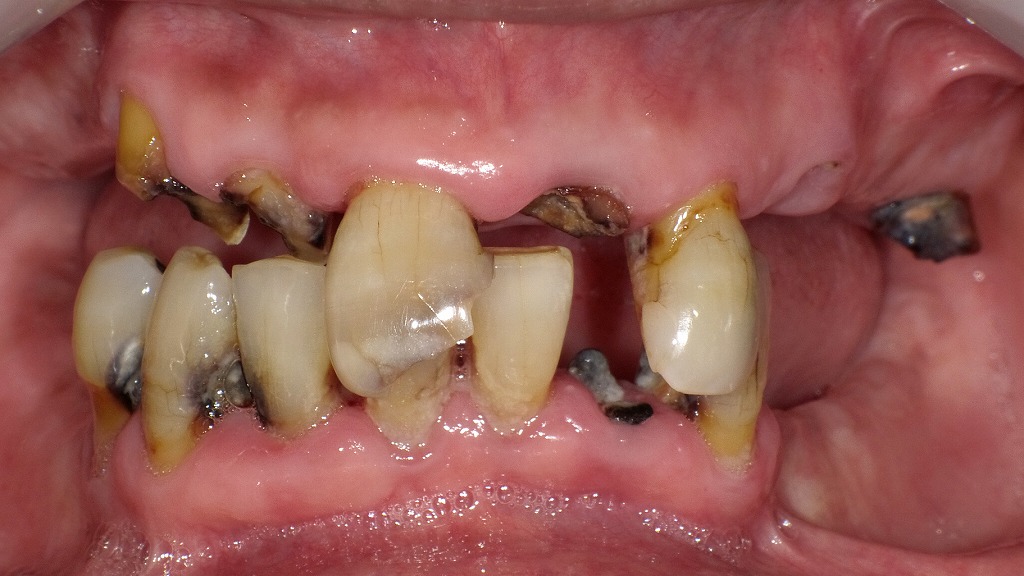

長年の虫歯と噛み合わせの崩れにより、歯がほとんど残っていない状態で来院された患者さまの症例です。

「もう噛めない」「見た目も気になる」とお悩みでしたが、残せる歯をできるだけ保存し、仮義歯・仮歯を使って少しずつ噛み合わせと見た目を整えました。

噛み合わせが崩壊した初診時の口腔内所見

この写真は初診時の口腔内を示しています。

上顎・下顎ともに多数の歯が重度に崩壊しており、歯冠がほとんど残っていない部位も多く見られます。残存歯は虫歯(う蝕)と歯石、着色が強く、咬合(かみ合わせ)の高さが失われている状態=咬合崩壊が明らかです。

① 重度虫歯(う蝕)

- 上顎・下顎の前歯・臼歯ともに、歯質が大きく欠損。

- 黒褐色の変色や崩壊部が多く、感染歯質が深部まで進行していると推察されます。

- 一部歯冠はほとんど消失し、根だけが残る「残根状態」になっています。

② 咬合崩壊

- 奥歯の喪失により、上下の咬み合わせが大幅に低下。

- 前歯に過剰な咬合圧が集中し、歯の傾斜や移動、隙間が見られます。

- 咀嚼機能が著しく低下しており、発音や審美にも影響している可能性があります。

③ 歯肉・粘膜の状態

- 歯肉は発赤し、炎症性の腫脹が疑われます。

- プラークコントロール不良による慢性歯周炎の併発が考えられます。

🩺 診断の方向性

- 多発性う蝕および重度歯周病を伴う咬合崩壊

- まずは感染源除去(抜歯・仮義歯による安定化)を行い、口腔内環境を整えた上で、**再建治療(義歯・インプラント・ブリッジなど)**を検討する必要があります。